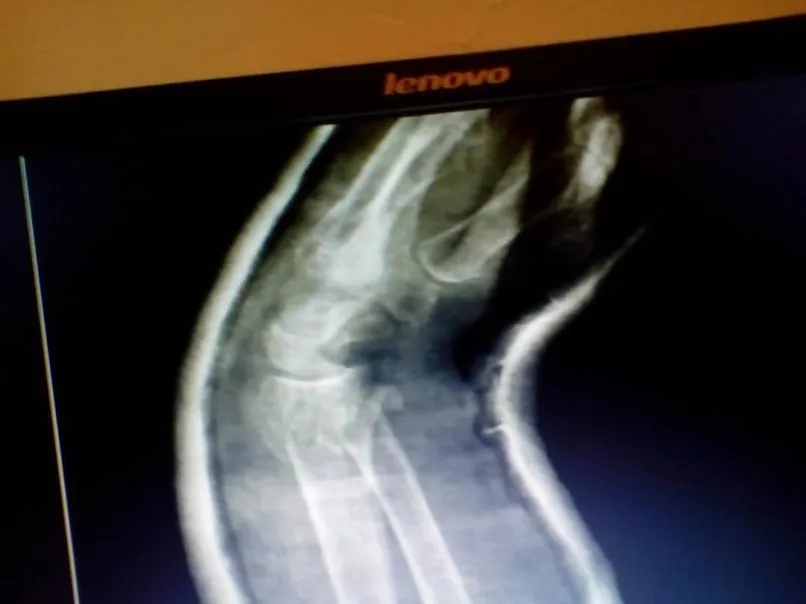

Para el día lunes se realizaron las imágenes de Rx de control para ver la evolución de la paciente